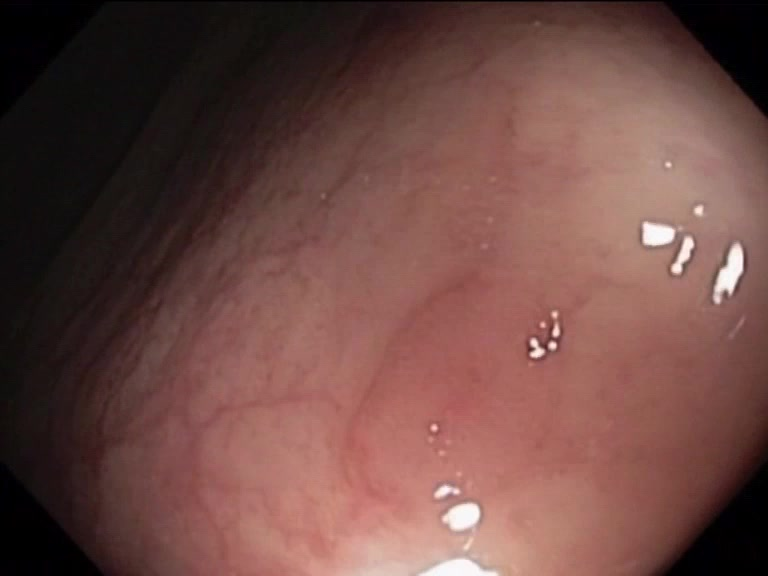

| Lesion | White Light Frame | NBI Frame | White Light Video | NBI Video | Camera Calibration |

| hyperplasic_01 |  |

|

WL.mp4 | NBI.mp4 | cam.xml |